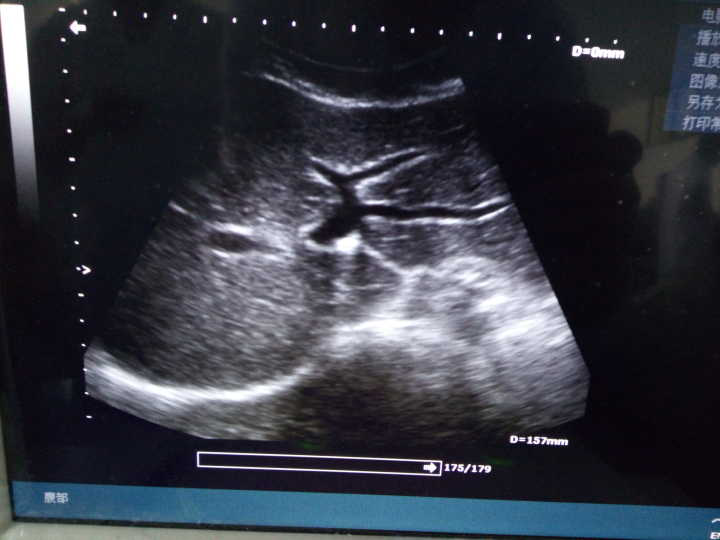

答:影像诊断培养的是放射医师,超声诊断培养的是超声医师,有诊断权,就业方向不同。

超声诊断:二年级全学年——超声诊断学

答:影像专业课程与临床紧密相关,在解剖学的基础上结合生理、病理、诊断、内、外、妇、儿等课程,根据影像图像做出诊断,协助临床医生确诊疾病。所以临床课程是基础,层层递进。